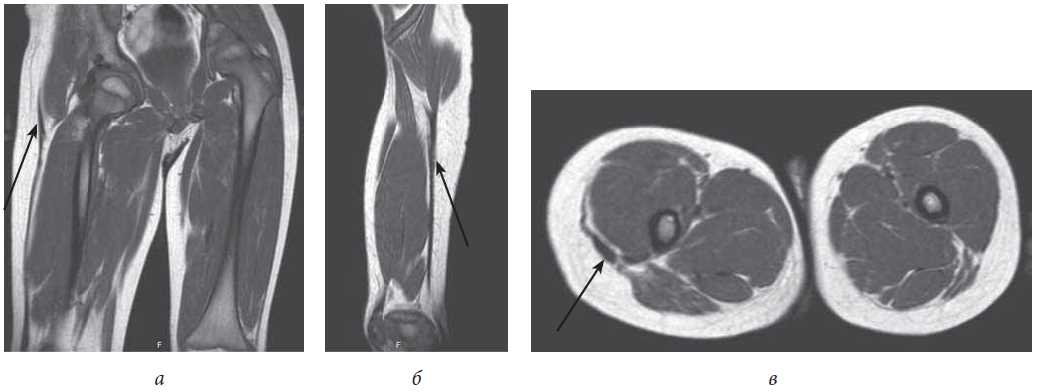

Magnetic resonance imaging (MRI) data were obtained using an MR tomograph Philips Panorama with a magnetic field induction of 1.0 T. Visualization of the fibrous cord in the soft tissues of the right thigh was most clearly determined using T1 weighted images (T1WI) in the coronary, sagittal, and axial planes (Fig. 4).

Fig. 4. CT sections in the coronary (a), sagittal (b), and axial (c) planes (arrows indicate thickened fibrous structures in the soft tissues of the right thigh)